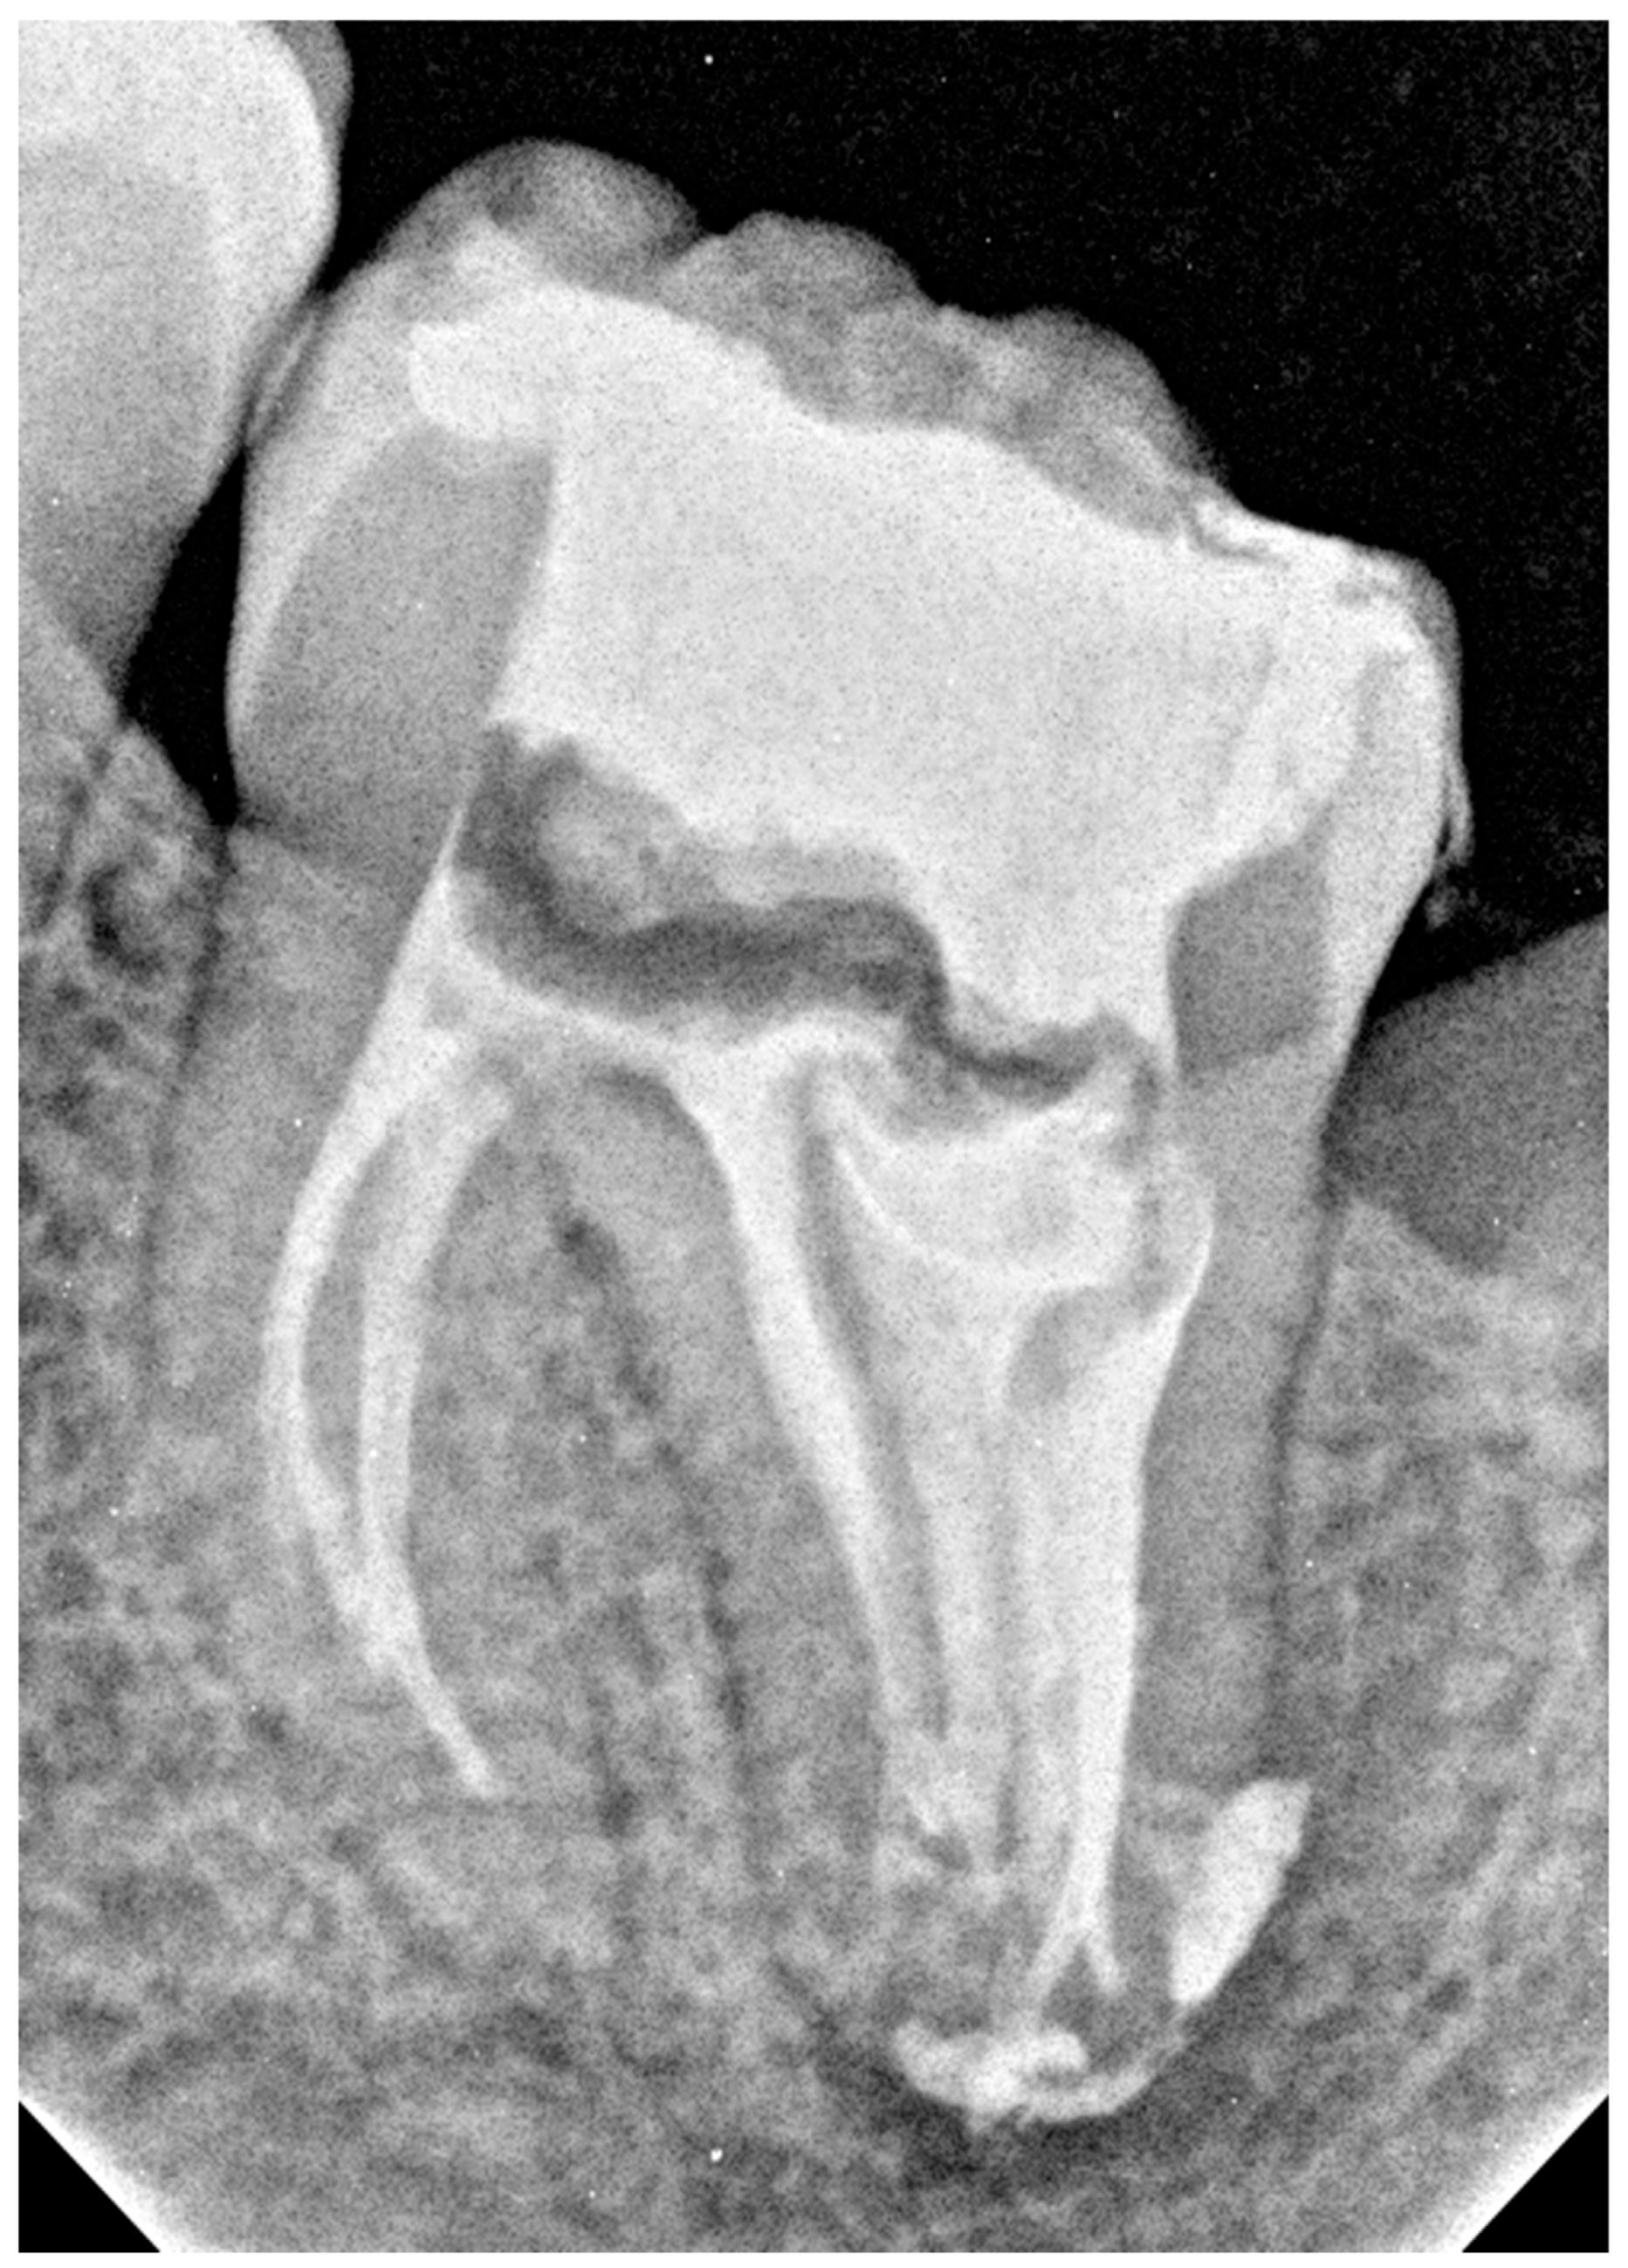

2. Case Presentation

2.1. The First Visit